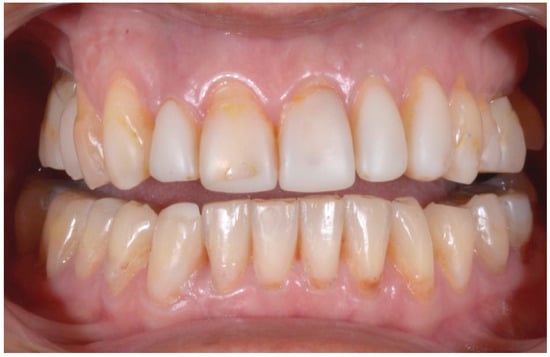

2.2. Clinical Example